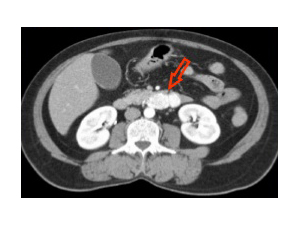

En el caso del Gist, las células precursoras son las denominadas Células de Cajal, llamadas así porque fueron descubiertas por el famoso histólogo D. Santiago Ramón y Cajal. Estas células se encuentran en la pared exterior del tubo digestivo junto a células musculares (que hacen que la comida circule por el tubo digestivo), actuando como marcapasos de las mismas (células nerviosas). Como estas células están situadas en el exterior, los tumores se inician en el exterior y generalmente no se expanden hacia el interior de los órganos, sino hacia el exterior, hacia los huecos que va encontrando en la cavidad abdominal. Y por esta misma razón, no suelen dar ningún síntoma hasta que no tienen un tamaño considerable, desarrollándose el tumor de forma silenciosa.

¿Dónde se desarrolla el Gist?

Los Gist se pueden desarrollar en cualquier parte del tracto gastrointestinal:

- Entre el 50-70% de todos los Gist se originanen el estómago.

- Entre el 20-30% en el intestino delgado.

- Entre el 5-15% en el intestino grueso y recto.

- En casos aislados, menos de 5%, también se pueden encontrar en el esófago o en la cavidad abdominal.